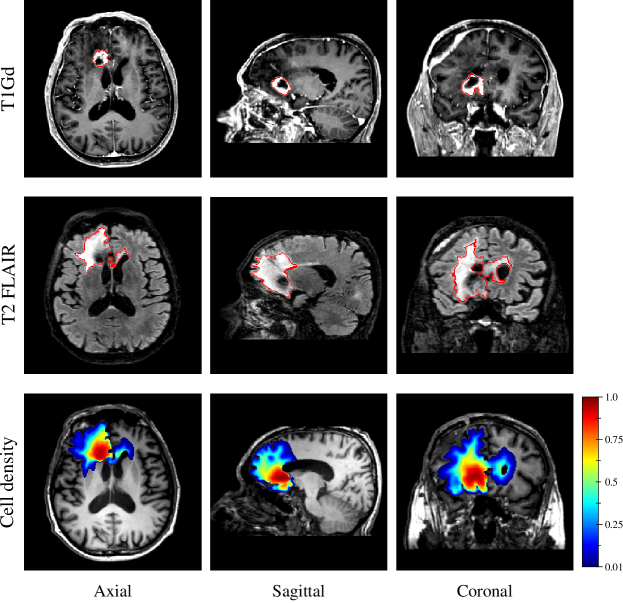

Finally, the estimated tumour cell distribution for the studied GBM patient provided by the first network (see Figure 5) is depicted in Figure 12 along with the T1Gd and T2 FLAIR images with superimposed segmented enhancing core and oedema contours, respectively.

Figure 12: T1Gd image (1st row), T2 FLAIR image (2nd row), and estimated tumour cell density distribution using the first network (3rd row) for an IDH-wildtype glioblastoma patient in axial (1st column), sagittal (2nd column), and coronal (3rd column) planes. The contours of the segmented enhancing core and peritumour vasogenic oedema are superimposed in red on the T1Gd (1st row) and T2 FLAIR (2nd row) images, respectively.